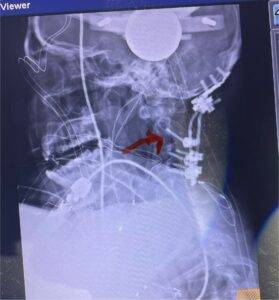

Cervical x-rays revealed a significantly increased atlanto-axial interval (Fig. 5) On review of her imaging studies it was noted that the right C2 isthmus was very thinned by the vertebral foramen (Figs 6a, b, and c) which would make an attempt at placing a C2 pars screw dangerous. A decision was made to perform an occipital-cervical fusion because only possible unilateral fixation and an extensive C1 laminectomy to be performed eliminating a fixation point if a more traditional C1-C2 was performed. Even if C1 lateral mass screws were able to be placed one could only perform a unilateral screw construct fixation to C2. We performed an occipital cervical fusion down to C4 to get enough inferior fixation and C1 laminectomy. The decompression went well. We placed a left unilateral pars screw and bilateral C3 and C4 lateral mass screws. We placed three 12 mm screws in the midline keel (Fig. 7). Postoperatively the patient had all around improvement in her symptoms and did not qualify for rehab. Her post op films at 6 weeks (Fig. 8)

Fig. 8: Intraoperative photograph demonstrating occipital-cervical construct and C1 laminectomy (blue dot). Note the 3 screws in the midline keel (blue arrow)

Fig. 12: Intraoperative lateral X-ray demonstrating good placement of occipital-cervical construct